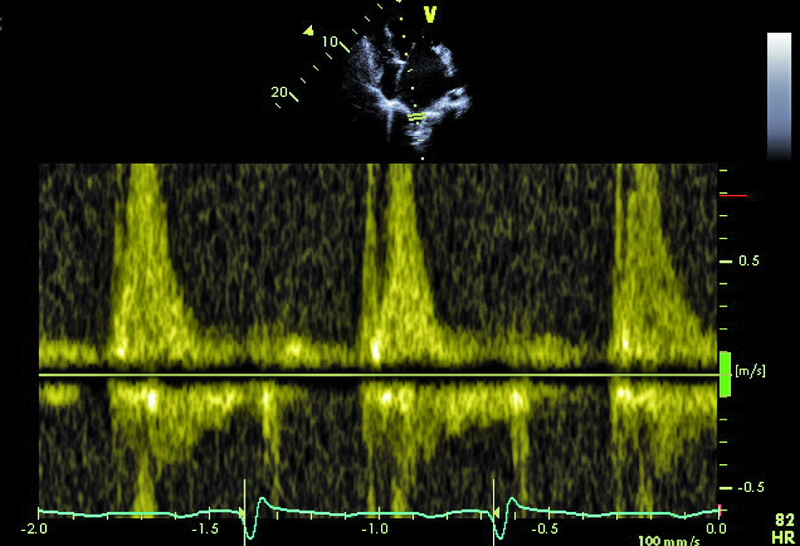

U chłopca, obecnie 16-letniego, wykonano w okresie noworodkowym zabieg operacyjny walwuloplastyki zastawki aortalnej z powodu wrodzonej stenozy. Uzyskano zmniejszenie gradientu maksymalnego z 50 do 16 mm Hg. W ciągu wielu lat obserwacji w ośrodku kardiologii dziecięcej gradienty przepływu przez zastawkę były niskie, a stan kliniczny pacjenta dobry. Sytuacja zmieniła się przed kilkoma miesiącami. Chłopiec został przyjęty do szpitala z powodu męczliwości, szybkiej częstości serca (do 90/min w rytmie zatokowym z pojedynczą ekstrasystolią komorową). Prawdopodobną przyczyną pogorszenia stanu zdrowia była przebyta wcześniej infekcja górnych dróg oddechowych. W badaniu przedmiotowym zwracał uwagę szmer holosystoliczny na koniuszku, promieniujący do pachy. W EKG rejestrowano cechy przerostu i przeciążenia mięśnia lewej komory. Wykonano cewnikowanie serca, stwierdzając nadciśnienie płucne ze średnim ciśnieniem w kapilarach płucnych 29 mm Hg. Pacjent był leczony intensywnie lekami moczopędnymi, beta-adrenolitykami i amiodaronem. Wobec braku poprawy skierowano go na oddział kardiologii dorosłych w celu rozważenia wskazań do leczenia operacyjnego. W badaniu echokardiograficznym zwracały uwagę wąskie strumienie niedomykalności zastawki aortalnej z czasem PHT wynoszącym 206 ms, istotnie powiększona jama lewego przedsionka z powierzchnią około 50 cm2, ciężkie nadciśnienie płucne z ciśnieniem skurczowym w jamie prawej komory 114 mm Hg!, rejestrowanym z małej fali zwrotnej trójdzielnej. Nie stwierdzono wady przeciekowej.

Chłopiec przebył w okresie noworodkowym zabieg walwuloplastyki aortalnej powikłany niedomykalnością zastawki (ryc. 1). Wada miała charakter przewlekły i spowodowała pojawienie się mechanizmów wyrównawczych. Jednym z nich jest zwiększenie objętości lewej komory i przyspieszenie rytmu serca. Frakcja wyrzutowa lewej komory jest zachowana (ryc. 2). Z pewnością infekcja górnych dróg oddechowych była czynnikiem inicjującym niekorzystny dla chorego przebieg zdarzeń. Ocena ciężkości niedomykalności aortalnej na podstawie parametrów ilościowych jest w tym przypadku trudna. Czas połowicznego spadku gradientu ciśnień PHT (aorta – lewa komora) oraz strumień fali zwrotnej w badaniu kolorowego doplera mogłyby wskazywać na umiarkowaną niedomykalność. Nie można jednak zapominać o możliwości zwiększenia ciśnienia rozkurczowego w jamie lewej komory, istotnie zmniejszającego gradient wsteczny i zakres fali zwrotnej. W przypadku dwustrumieniowej fali zwrotnej (jak w tym przypadku) talii cząstkowych niedomykalności nie sumuje się. Podobnie ograniczone zastosowanie w tym wypadku (ekscentryczne fale zwrotne) ma metoda ERO. Najprawdopodobniej wtórną do niedomykalności aortalnej wadą jest niedomykalność mitralna wynikająca z poszerzenia jamy lewej komory i poszerzenia pierścienia zastawki mitralnej. Niedomykalność mitralna także wydaje się co najwyżej umiarkowana (ryc. 3). Należy pamiętać, że i w tym wypadku szerokość strumienia fali zwrotnej zależy od wysokości ciśnienia w jamie przyjmującej, czyli w lewym przedsionku. Na podstawie przedstawionego materiału (ryc. 4-6) można stwierdzić, że nadciśnienie płucne u chłopca (postkapilarne) jest ciężkie, a ciśnienia uległy istotnemu zwiększeniu w porównaniu z wartościami stwierdzanymi wcześniej podczas cewnikowania serca (ciśnienie rozkurczowe płucne 54 mm Hg, średnie 74 mm Hg!). Warto zwrócić uwagę na profil spływu z żył płucnych. Zaznacza się w nim bardzo krótka faza odzwierciedlająca wyłącznie rozkurczowy napływ krwi do lewego przedsionka. Zwiększona objętość jamy przedsionka, wysokie ciśnienie krwi w niej panujące oraz ograniczona podatność ściany sprawiają, że w fazie skurczu komory nie rejestruje się napływu do jamy przedsionka. Podobnie bardzo wysokie ciśnienie w układzie żył płucnych sprawia, że nie obserwuje się przepływu wstecznego w związku z ciągle zachowanym skurczem przedsionka (rytm zatokowy). Chłopca zakwalifikowano do operacji dwuzastawkowej z powodu ciężkiej niedomykalności aortalnej i mitralnej. Zabieg implantacji zastawki biologicznej o średnicy 23 mm w ujście aortalne oraz pierścienia o średnicy 32 mm w ujście mitralne przyniósł dobry efekt.